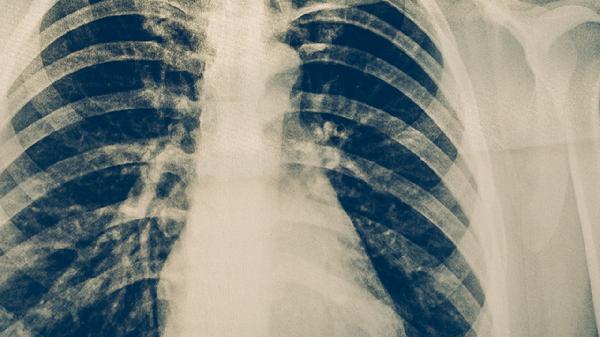

肺心病可能由慢性阻塞性肺疾病、肺动脉高压、支气管扩张、睡眠呼吸暂停低通气综合征、先天性心脏病等原因引起,肺心病可通过氧疗、药物治疗、手术治疗、生活方式调整、康复训练等方式治疗。